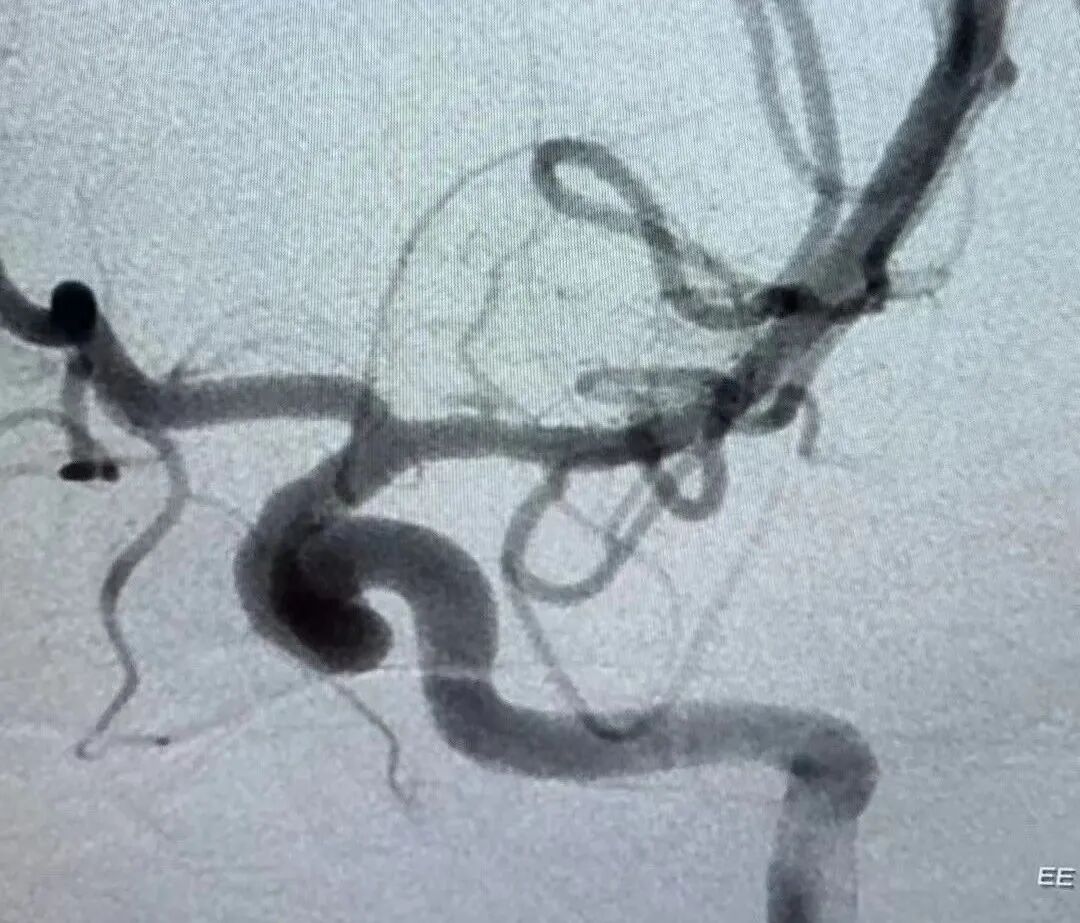

患兒病情急迫,神經(jīng)外科腦血管病區(qū)景英朝主任醫(yī)師及其團(tuán)隊(duì)?wèi){借多年的臨床治療經(jīng)驗(yàn),評估后制定了進(jìn)一步完善腦血管造影(DSA)檢查,同時備好介入栓塞術(shù)治療。

最終,小霖經(jīng)腦卒中綠色通道,迅速完成術(shù)前準(zhǔn)備并送入介入室。在與介入室、急診科、麻醉科的通力合作下,神經(jīng)外科血管組景英朝團(tuán)隊(duì)歷時2個小時,順利完成手術(shù),小霖的腦血管畸形被順利栓塞,手術(shù)獲得圓滿成功。

術(shù)前腦血管畸形團(tuán)